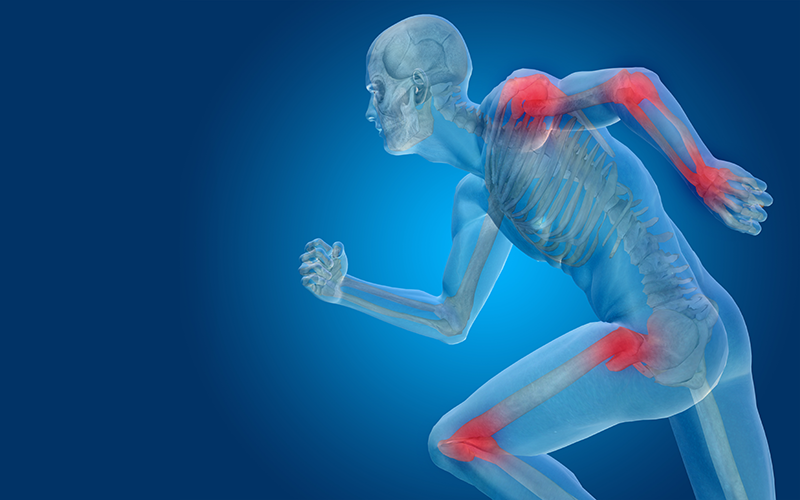

Orthopedics at Mata Chandrakala Hospital stands as a vital medical specialty dedicated to diagnosing and treating a wide array of musculoskeletal conditions, including fractures, joint disorders, and spinal issues. Orthopedic doctors at Mata Chandrakala Hospital employ a spectrum of treatments, ranging from conservative approaches like physical therapy and medications to sophisticated surgical interventions such as joint replacements, all aimed at restoring mobility, alleviating pain, and enhancing overall function for patients.

The scope of orthopedic care at Mata Chandrakala Hospital encompasses diverse conditions affecting bones, joints, muscles, ligaments, and tendons, necessitating personalized treatment plans tailored to each patient's unique needs and circumstances. Orthopedic specialists at Mata Chandrakala Hospital collaborate closely with other healthcare professionals to deliver comprehensive care, addressing not just the immediate issue but also considering the patient's